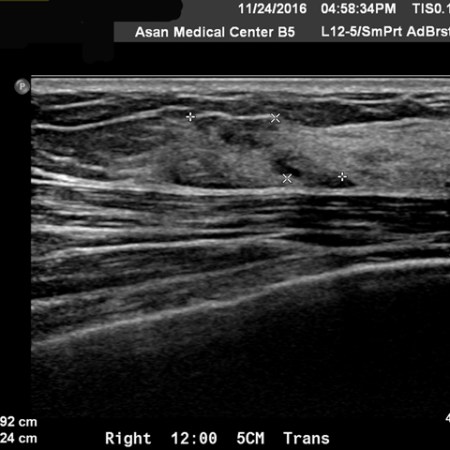

유방암 11강 – 수술 후 tamoxifen을 사용한 소양인 유방암 환자 이야기

유방암 10강 – 유방암3기 – 양방치료를 거부한 소양인 유방암 환자이야기 – 양측성 종양과 겨드랑이 림프절 전이